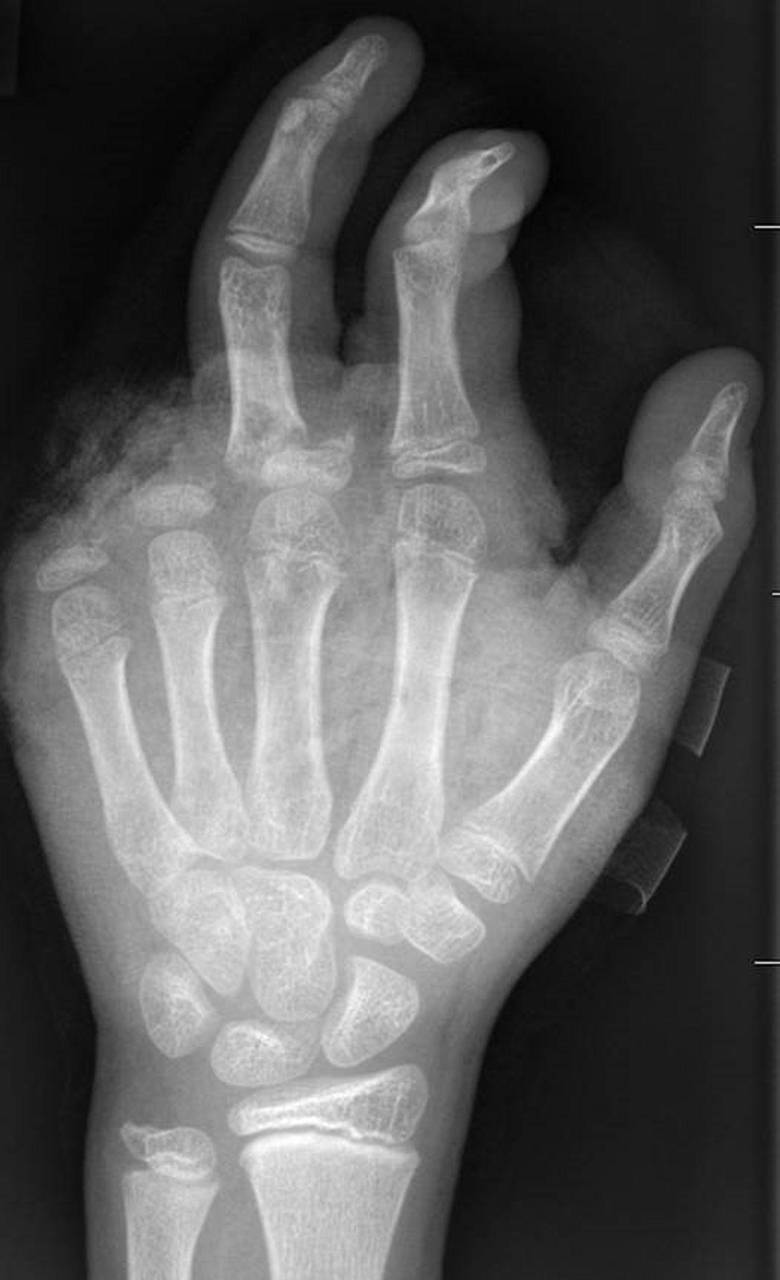

Berlin (dpa) - Abgetrennte Finger, durchtrennte Sehnen, Amputationen - die Handchirurgin Leila Harhaus-Wähner hat in der Silvesternacht schon vieles gesehen. Auch in diesem Jahr rechnet die Berliner Ärztin mit zahlreichen Böller-Verletzten. «Für Handchirurgen ist es klar, dass Silvester die arbeitsreichste Nacht sein kann.» Bis 24 Uhr passiere erstmal nicht so viel, ab 1 Uhr, 2 Uhr nachts kämen immer mehr Verletzte in die Notaufnahme und dann «sehr viele in sehr kurzer Zeit.»

In der Handchirurgie müssten an Silvester im Unfallkrankenhaus rund 20 bis 40 Menschen mit Böllerverletzungen operiert werden, sagt die Ärztin. Dieses Jahr werde sie mir vier weiteren Handchirurgen im Einsatz sein. Die häufigsten Verletzungen entstünden durch explodierende Böller in der Hand.

«Der überwiegende Teil der Verletzungen trägt tatsächlich lebenslange Folgen mit sich, weil die Sprengkraft dazu führt, dass eben nicht nur einzelne Strukturen verletzt sind, sondern immer mehrere. Und das heilt praktisch nie ganz folgenlos ab.» Zum Teil könnten Hände nicht mehr gerettet und müssten amputiert werden.

Für eine neue Dimension habe im vergangenen Jahr das illegale Abbrennen von Kugelbomben gesorgt. «Die Patienten mit Verletzungen durch Kugelbomben weisen sehr viel stärkere Verletzungsmuster auf, die auch den ganzen Körper betreffen, weil diese Explosion ungerichtet stattfindet. Und das sind nicht nur Hände und Gesichter, sondern auch Bauch, Beine.» Alle Körperareale seien gleichermaßen gefährdet.